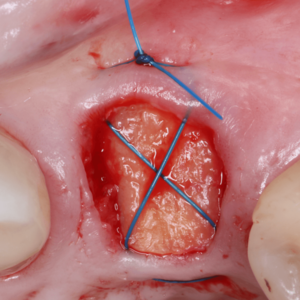

Strategien zum Weichgewebeerhalt nach Sofortimplantation in der ästhetischen Zone

In der ästhetischen Zone erfordert die Sofortimplantation besondere Sorgfalt,

um langfristig stabile und ästhetisch überzeugende Ergebnisse zu gewährleisten. Ein Schlüssel hierzu liegt

im Erhalt und der Stabilität des Weichgewebes. Das BAP-Konzept bietet innovative Strategien für diese Herausforderungen.